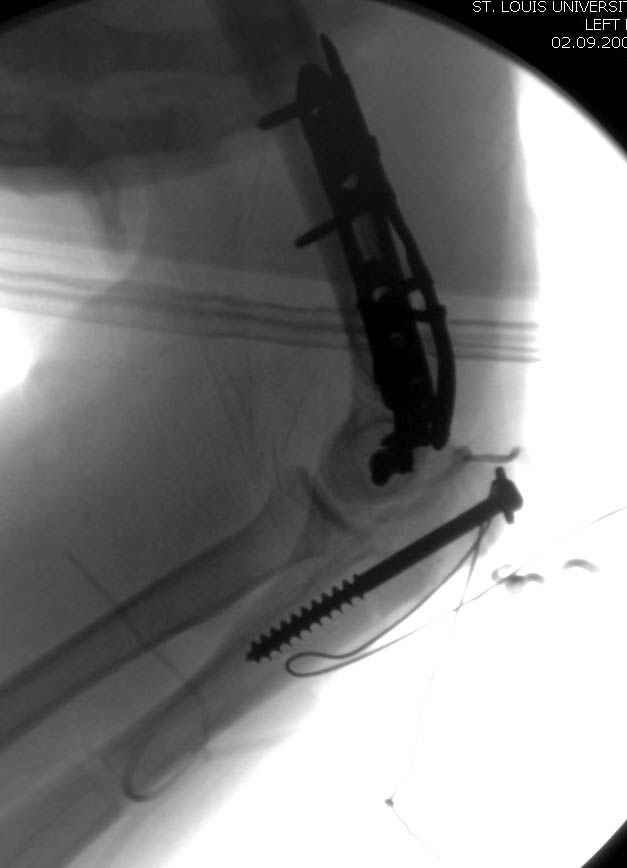

Djoldas Kuldjanov, M.D. 09 Сентябрь 2005, 20:07

Примерный случай, только перелом был открытый, в задне-медиальной стороне рана около 2 см по характеру "изнутри кнаружи", неврологический статус со слабостью сгибания мизинца, также слабая абдукция и аддукция указательного пальца и сгибания в кисти.

Больному сделали обработку и наложили временный аппарат внешной фиксации плечо-предплечье.

На шестой день сделали открытую репозицию чрезлоктевым доступом двумя locking plate, локтевой нерв был ушибленным, после операции положительная динамика в Flexor Carpi Ulnaris. Фиксацию локтевого отростка произвели tension band technique с дополнительным шурупом.

Этапы операции на снимках....

Джолдас Кульджанов

Djoldas Kuldjanov, MD

Department of Orthopedic Surgery

St. Louis University Medical Center